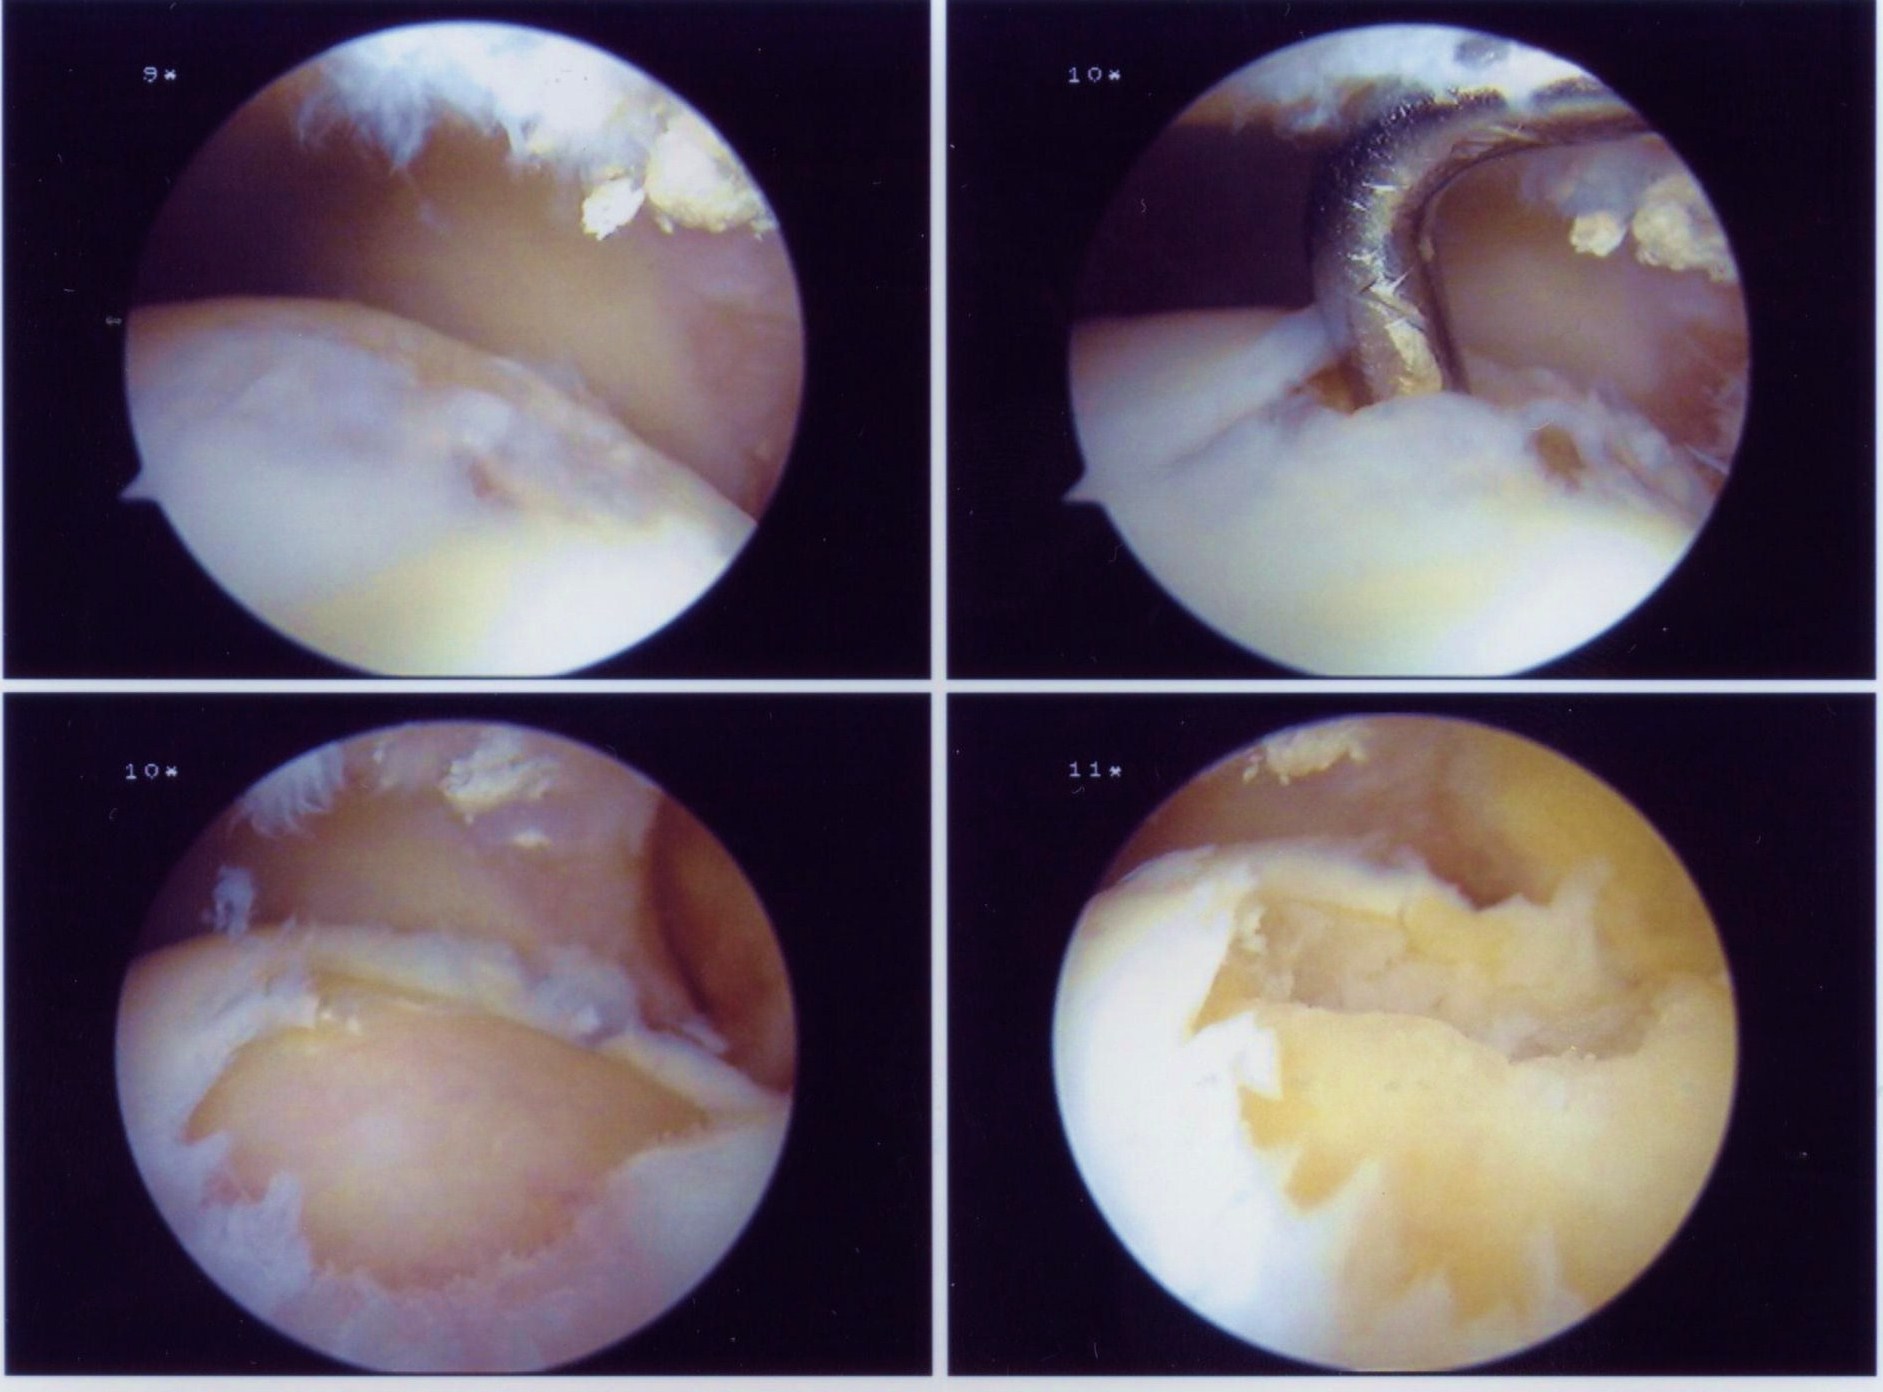

Treatment consisted of an arthroscopic excision of the talar dome osteochondral lesion together with microfracture of the bony base to stimulate fibrocartilage formation.

Video of the right ankle arthroscopy.

Part 1 – Probing the Lesion

Part 2 – Debriding the osteochondral lesion

Part 3 – Microfracture of the Bony Defect